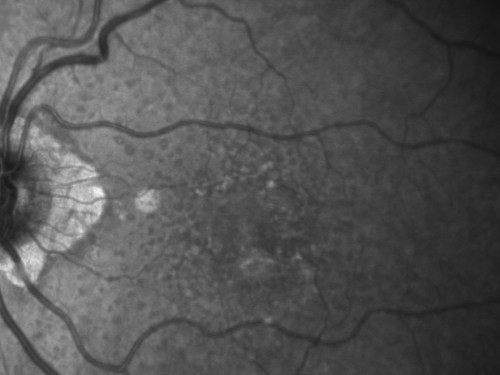

Reticular Macular Disease (Pseudo-drusen) Both Eyes - Wet AMD OS - Dry AMD OD InfraRed

84-year-old woman has wet age-related macular degeneration in the left eye and dry macular degeneration in the right eye.  She takes the eye vitamins and her vision is stable since she was treated three months ago with Avastin.   OD 20/50,  OS 20/32